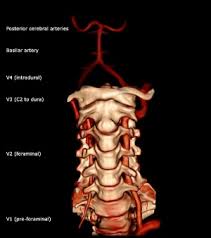

Vertebrobasilar Stroke Overview Anatomy Of The Vertebral And Basilar Arteries Pathophysiology Of Vertebrobasilar Stroke